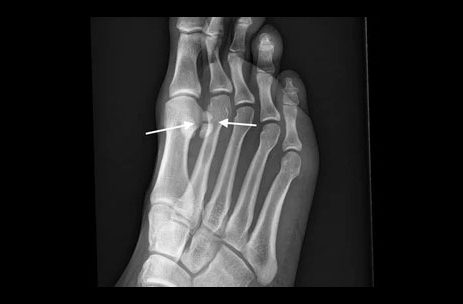

Sesamoiditis Fracture

There are two round bones located directly beneath the big to joint in the ball of the foot. These bones are located in the muscle of the foot and are not connected to any other bones (similar to a knee-cap that glides in the knee joint). These round bones are responsible for bearing weight and assisting the big toe when you need to balance, run, and jump. A Sesamoiditis Fracture occurs when the joint of the big toe experiences too much weight over time or an injury. Sesamoiditis Fractures can also lead to Turf Toe. WHAT CAUSES A SESAMOIDITIS FRACTURE? A Sesamoiditis...